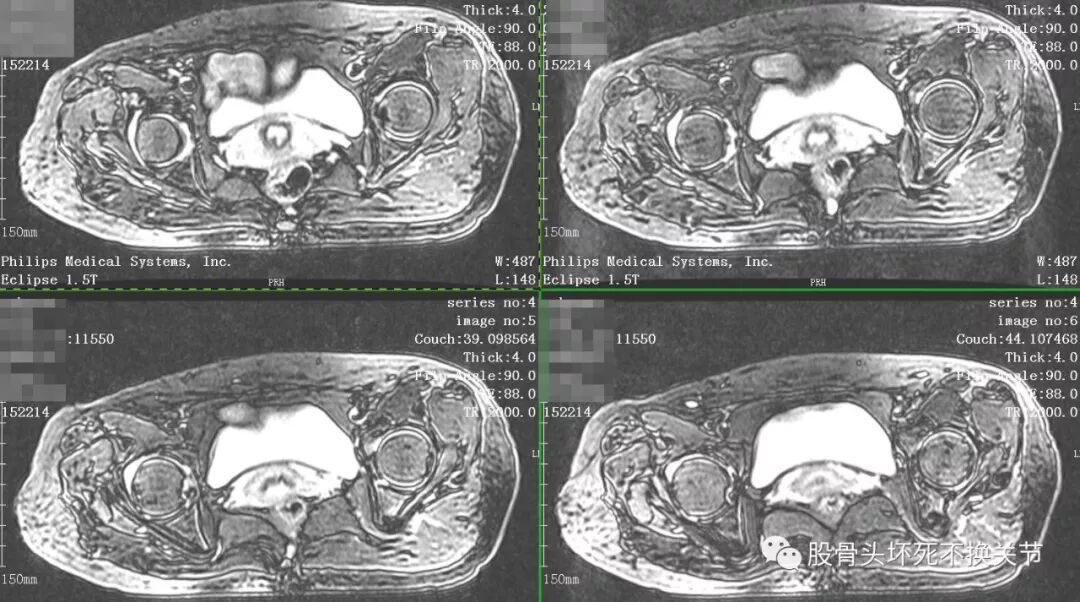

核磁共振是诊断疑难疾病的必备检查,更是诊断滑膜炎最直观、生动的手段。

点击放大观看双侧髋关节核磁共振片:

核磁共振检查显示右侧股骨头周围一圈亮度均匀的白色信号,就是平常所说的关节积液。